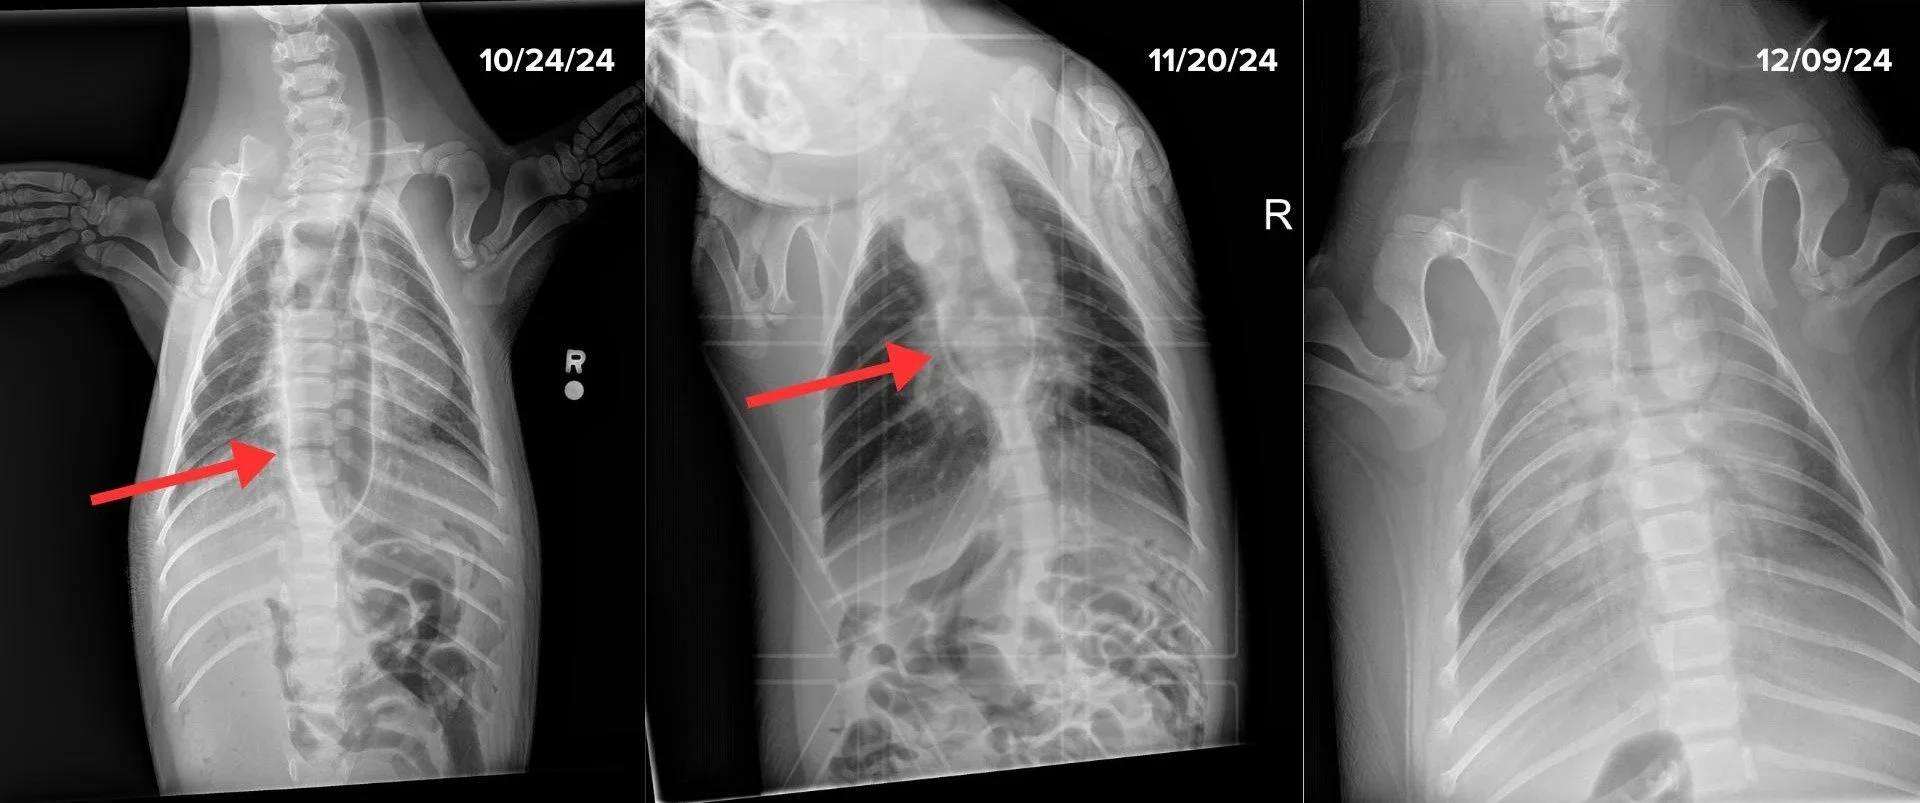

To diagnose this disorder we take x-rays of the patients. The enlarged esophagus is visible in the x-rays, and with successful treatment, we can see the esophagus shrink back to its normal size.

X-rays of Naga’s chest. A red arrow in the first two images points to her megaesophagus. It gets smaller in the middle image and her esophagus has returned to its normal size by the third.